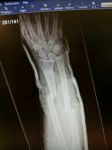

Not really ok, damage to front of my bike,

double open fracture to right foearm, broken and dislocated left thumb, stitches to right knee!

Loose horse ran straight over me even though i had stopped in the road!

Attachments

Damn looks nasty, I snapped my humerous through in my upper right arm years back and it seemed to take forever for the bones to nit back together. Yes you should most definitely make the owner PAY! Poor TTR cry